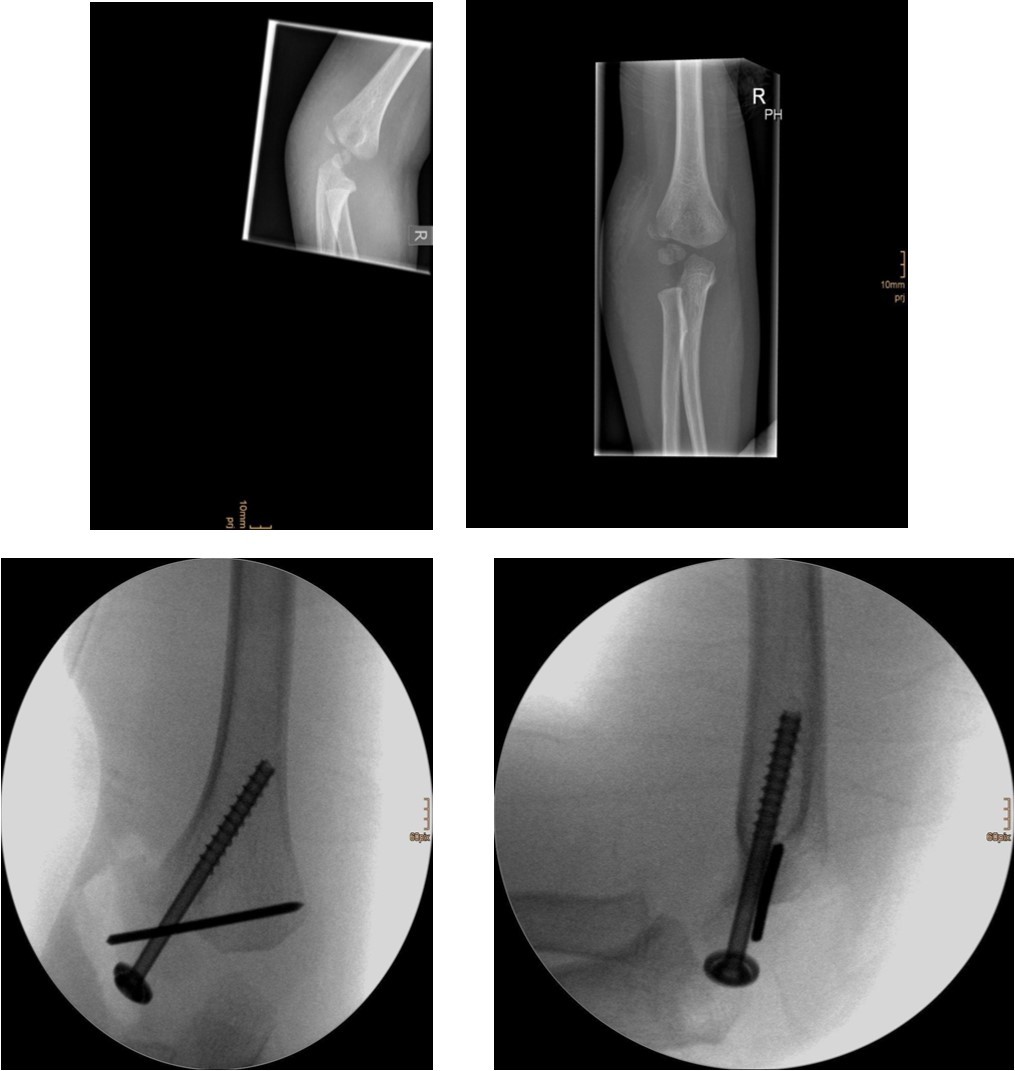

The fracture fragment can be approached by a posteromedial incision that allows good exposure of both the fracture site and the ulnar nerve. Fixation is easily achieved with smooth K-wires or with screws in older adolescents. Two wires are necessary because of the sagittal rotation forces exerted on the fracture fragment by the common flexor muscles. Figure 4 and Figure 5.

Figure 5.9 year old female patient with a elbow dislocation and a dislocated right medial condyle fracture which was treated by open reduction and osteosynthesis with a screw (personal collection)

9 year old female patient with a elbow dislocation and a dislocated right medial condyle fracture which was treated by open reduction and osteosynthesis with a screw (personal collection)